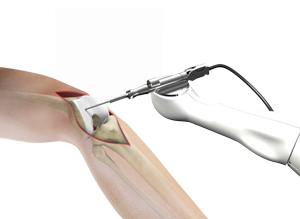

Patellar Tendon Repair

Patellar Tendon Repair Surgeon in Palm Beach Gardens & Wellington Patellar tendon repair is the surgery performed to reattach the torn tendon …